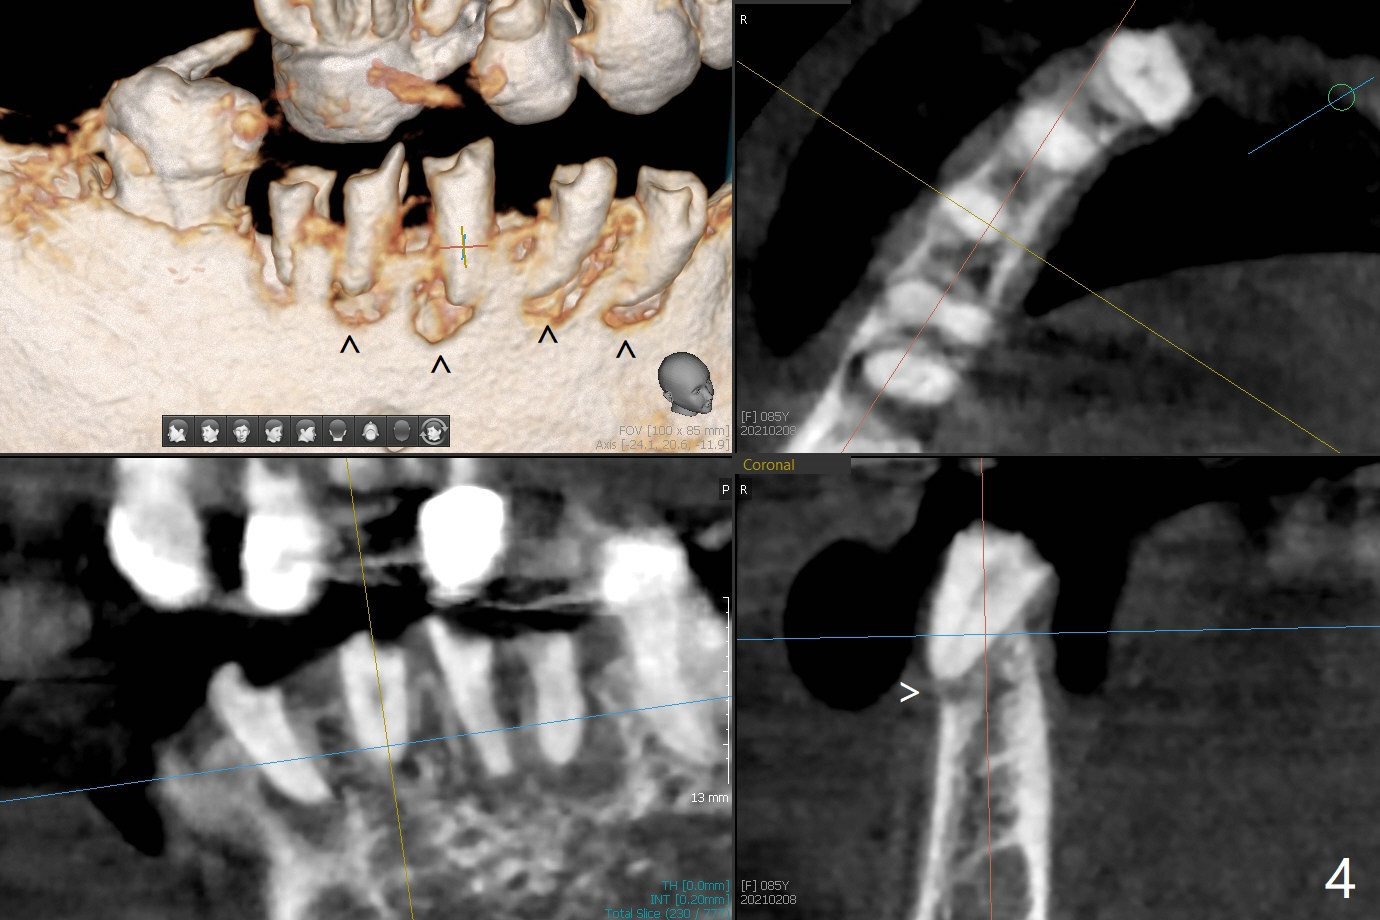

85岁女回诊所做27,28,30植牙,由于导板设计,所有7个残根需要拔除(图一,三),做过根管治疗牙齿(图一:箭头),如19,21号牙,颊侧骨板吸收比没做过的轻(图二,四:箭头(根尖穿孔))。30号牙根尖吸收多,使用短小植体(图五),根尖骨质少,初步稳定性差,不能即刻修复(图六),是这次手术最大欠缺的部分。原来准备在30号牙位做临时牙冠,局部托牙卡环恢复作用,还好27,28植体(图八)稳定性好,连体临时牙冠帮助托牙固定。27,28植体不足之处是放置太深,基台与牙槽骨(图八:*)接触,可能造成骨质吸收。其实27号植体(3.5x9mm)植入后必须去除,与基台连接后,一起徒手植入,所以深度控制不好。术后一个月10天病人回来做20和22号牙种植(拔牙后一,两个月),由于角化龈窄,切开导板植入,好处容易判断22号牙植体深度,植深后,两个植体周围放置骨粉(图九,十),然后胎盘膜(两个8x8毫米),4-0 PGA缝线。